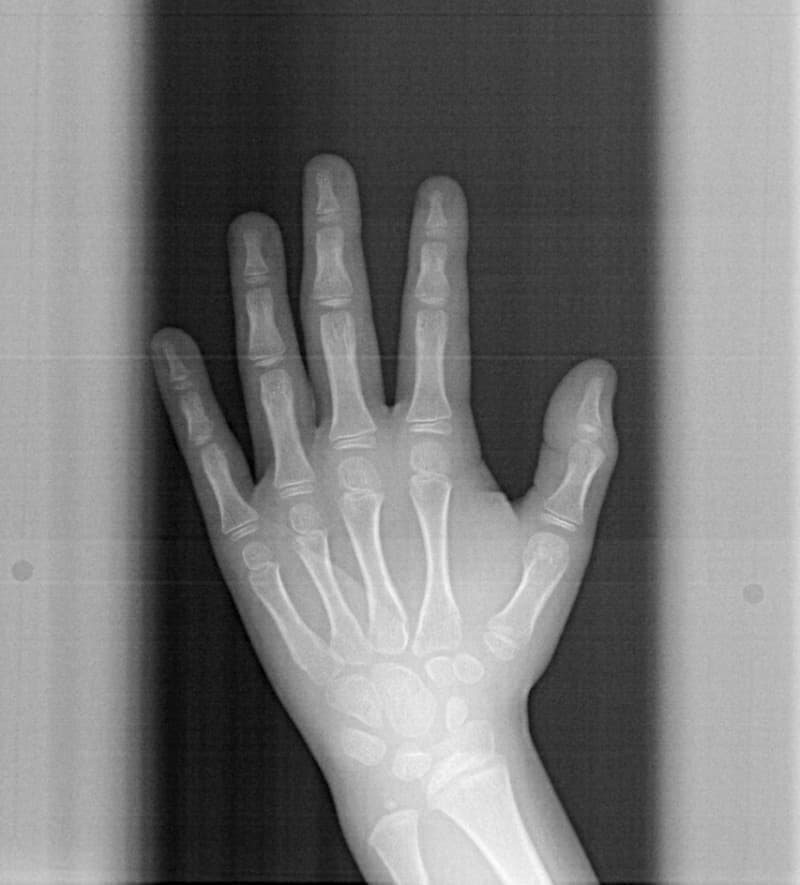

手根骨の骨年齢は実年齢よりも低く男児なので、今後旺盛な下顎の成長が予測されます。